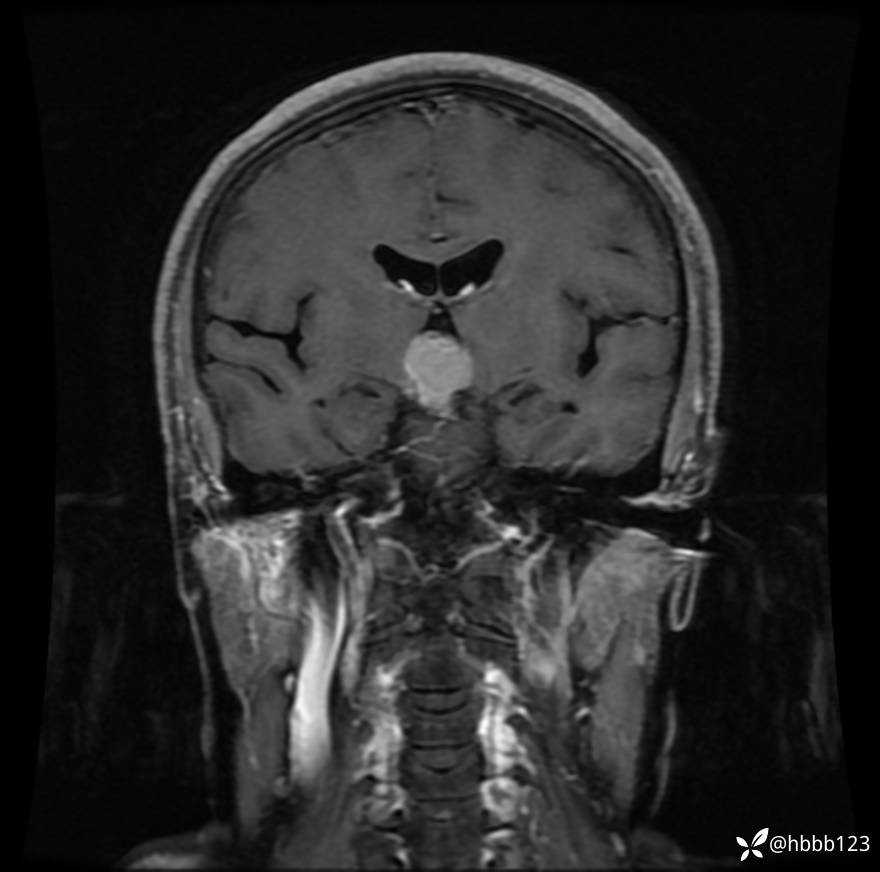

颅脑MRI平扫+增强扫描:

T1WI 增强 冠状位重建: